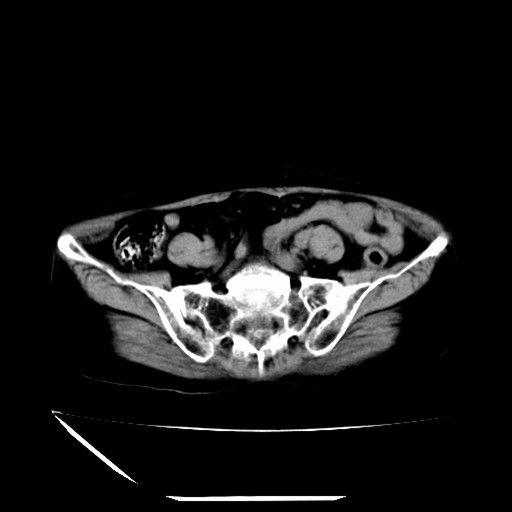

标题: CT16840:女-63岁,下腹部疼痛, [打印本页]

标题: CT16840:女-63岁,下腹部疼痛,

补充资料:血象是13.5,临床拟诊阑尾炎

本人诊断是右肾周围炎,阑尾炎,盆腔少许积液!

诊断右肾周围炎是因为我图像没有发完,诊断阑尾炎是因为相当于阑尾区连续两个层面可以看到增粗的阑尾显影。

支持阑尾炎!局部腹膜增厚,脂肪密度增高。应该手术治疗。